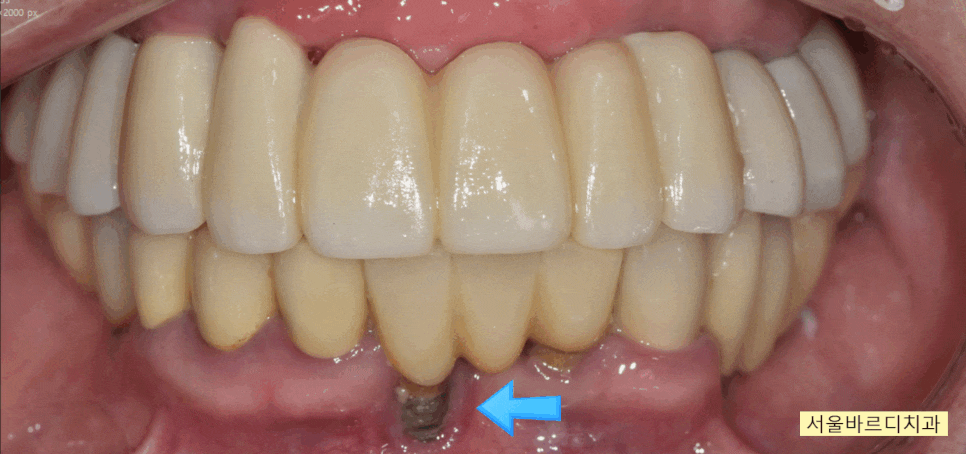

입술을 자꾸 씹어서 불편해요

상일동 치과에 내원해주신

80대 여자 환자분입니다.

현재 윗니 치아의 경우 부분 틀니를 사용중이신데

음식을 먹을 수가 없다 하셨습니다.

자꾸 질겅질겅 입술을 씹다보니

상처가 나서 아프고

편하게 식사도 못하시고 말이죠~~

검사를 해보니

치아가 전반적으로 윗니, 아랫니 사이

높이 차이가 크지 않습니다.

자연치아가 앞니만 남아있고

어금니 부위 치아가 상실되고 오랜 시간이 흐르다 보니

교합이 무너졌습니다.

틀니 점검을 주기적으로 오셨어야했는데...

한동안 치과 내원을 안하셨다 하네요..

틀니가 치아가 있던 공간을 대체해주지 못하면서

더 빨리 무너지게 되었고

(뼈 흡수도 급속도로 진행...)

위아래 높이 차이가 거의 안나다 보니..

음식을 씹는게 아니라

입술을 씹게 되셨습니다.